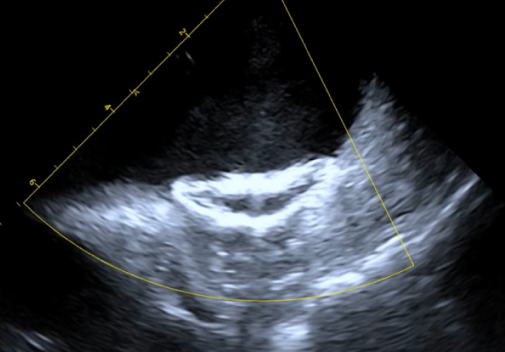

超声评估封堵效果满意